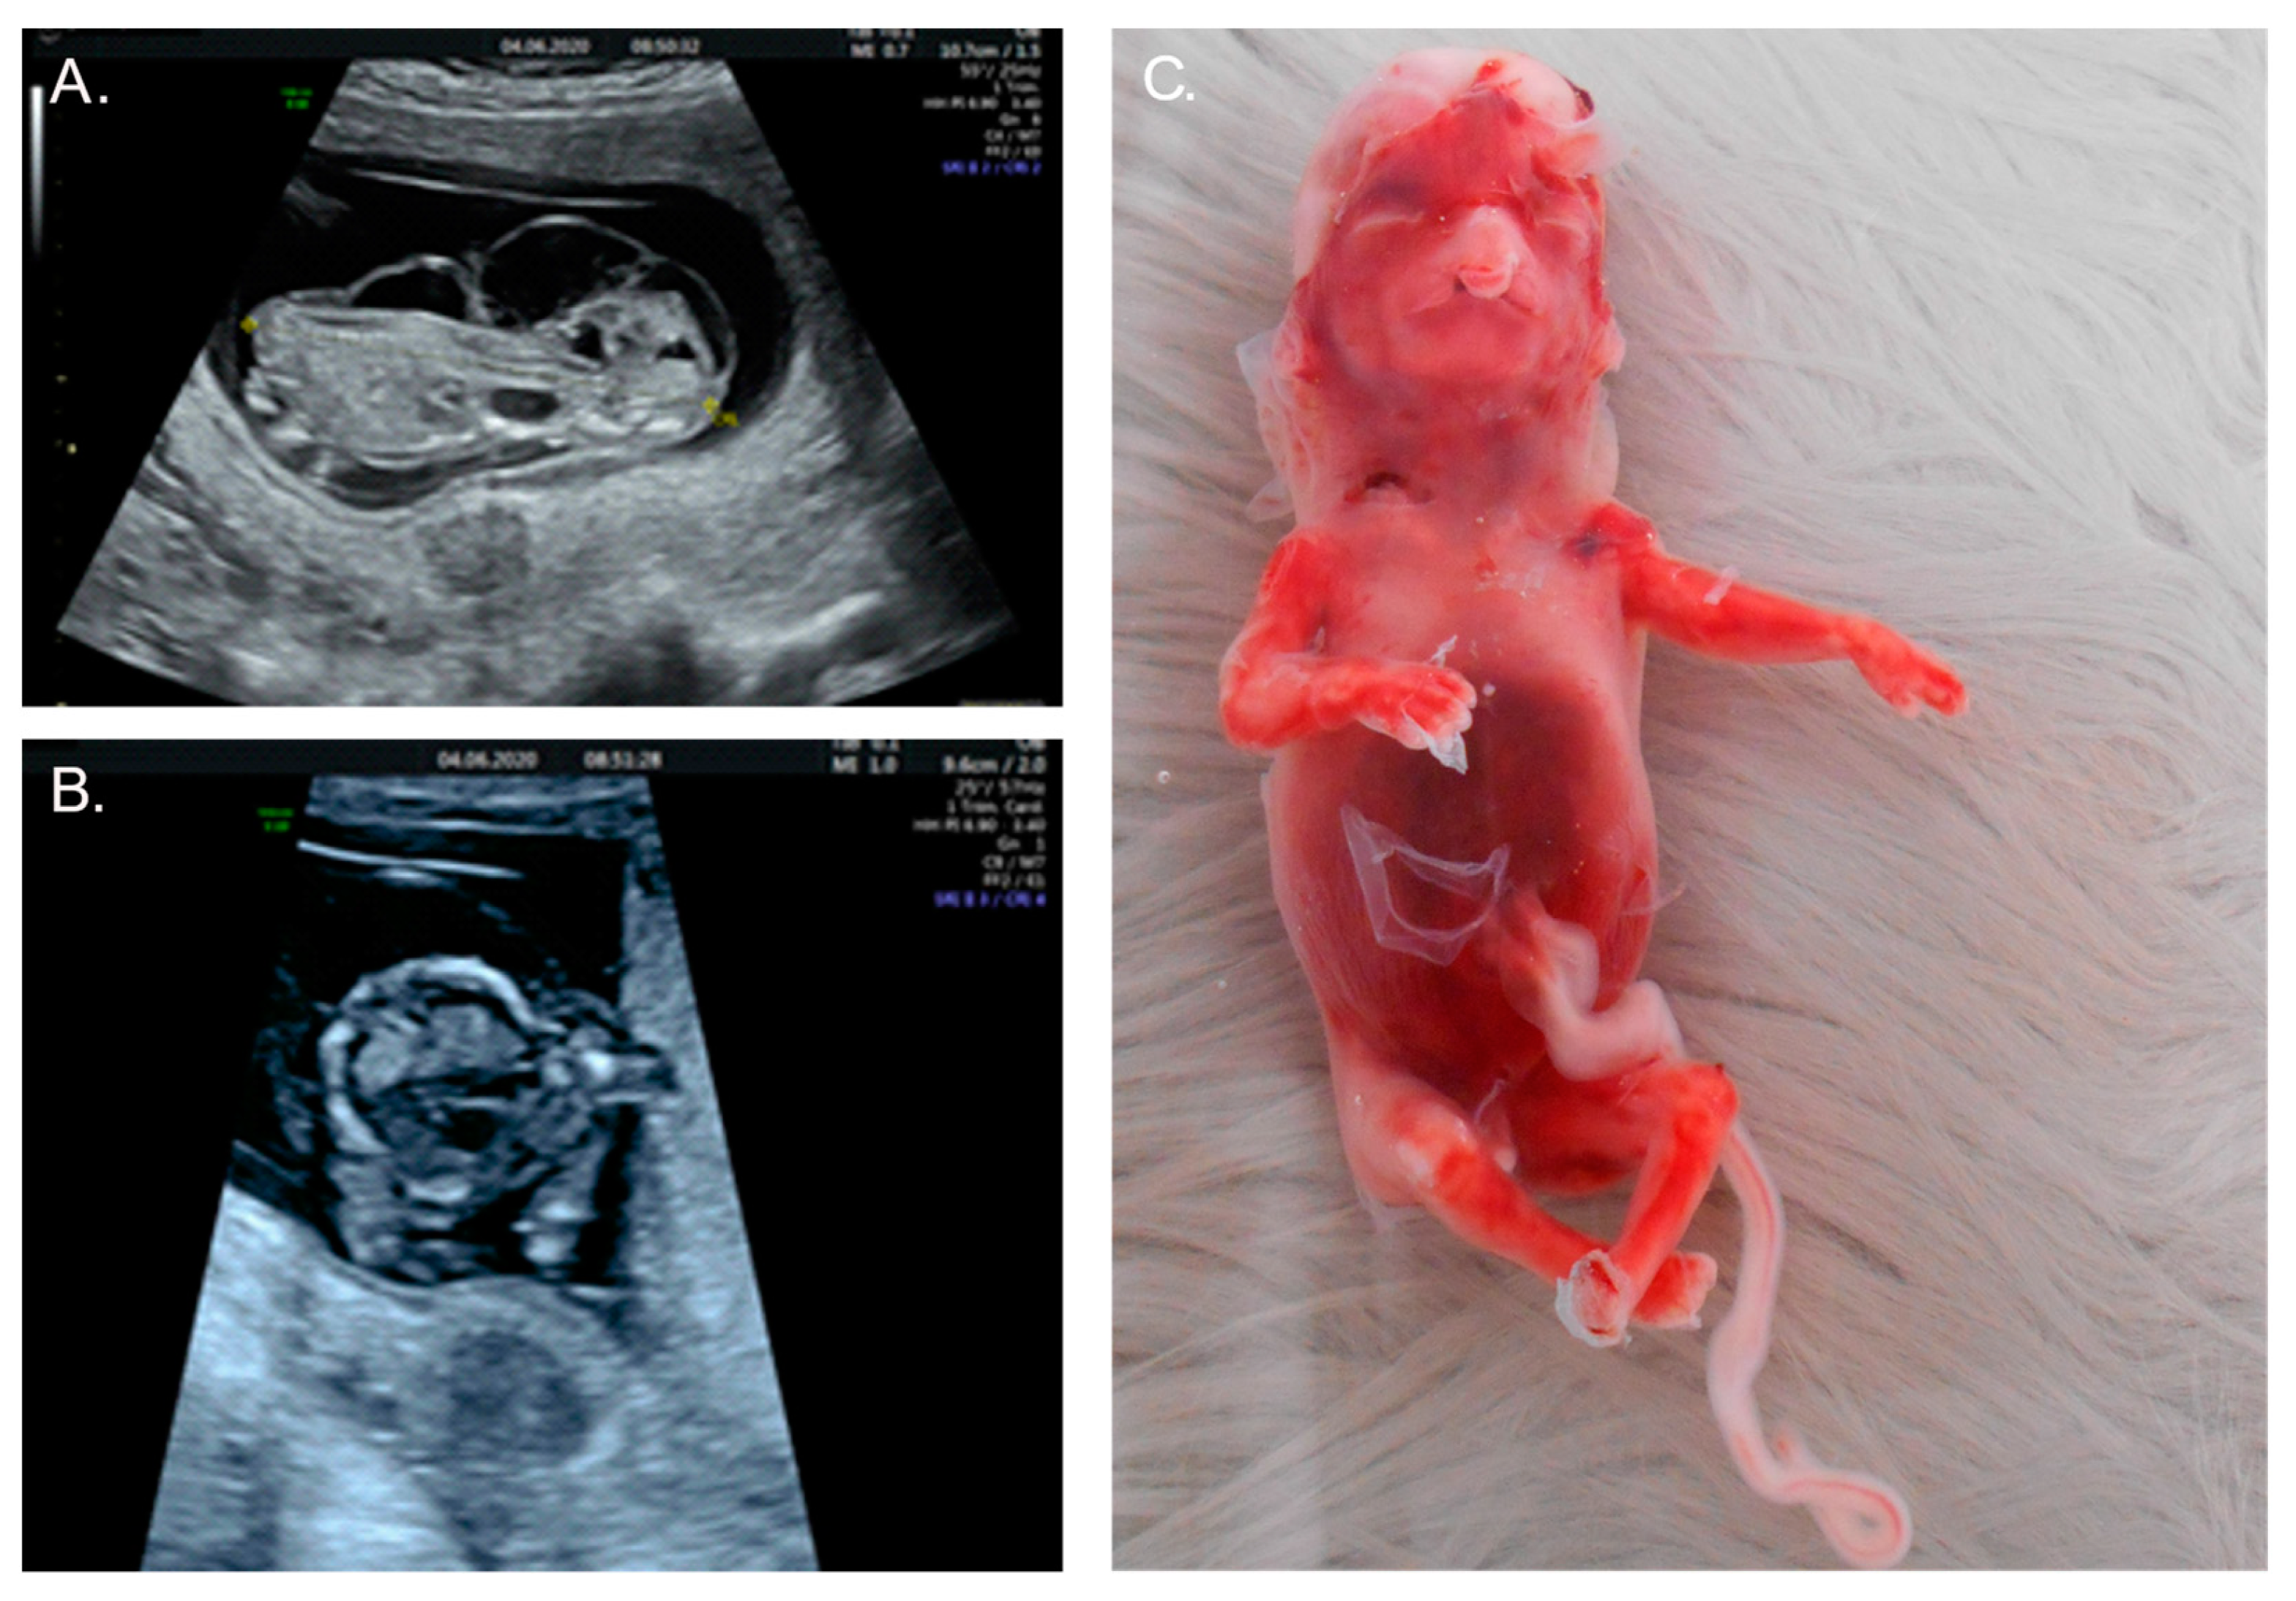

2.2. Case 2

| CNS anomalies (n = 12; 55%) | − | + | [1,5,7,12,14,15,16,17,18,19,20,21] |

| Cleft lip/palate (n = 10; 45%) | − | + | [1,3,5,12,16,19,21,23] |

| Facial dysmorphism (n = 8; 36%) | − | + | [1,3,5,7,20,21,23] |

| Cardiac anomalies (n = 5; 23%) | − | + | [12,16,20,21,25] |

| Absent nasal bone (n = 2; 9%) | − | + | [1,13] |

| Hydrops fetalis (n = 1; 5%) | − | + | [6] |